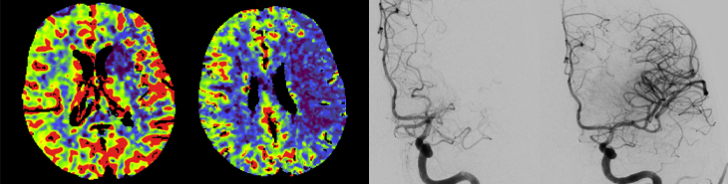

Diagnostically and therapeutically, the most modern methods and equipment are available for our patients. In addition to diagnostic neuroradiology, our clinic is characterized by a high level of expertise in minimally invasive neuroradiological therapy, both in the emergency treatment of strokes and in the elective treatment of aneurysms, vascular stenoses and vascular malformations.